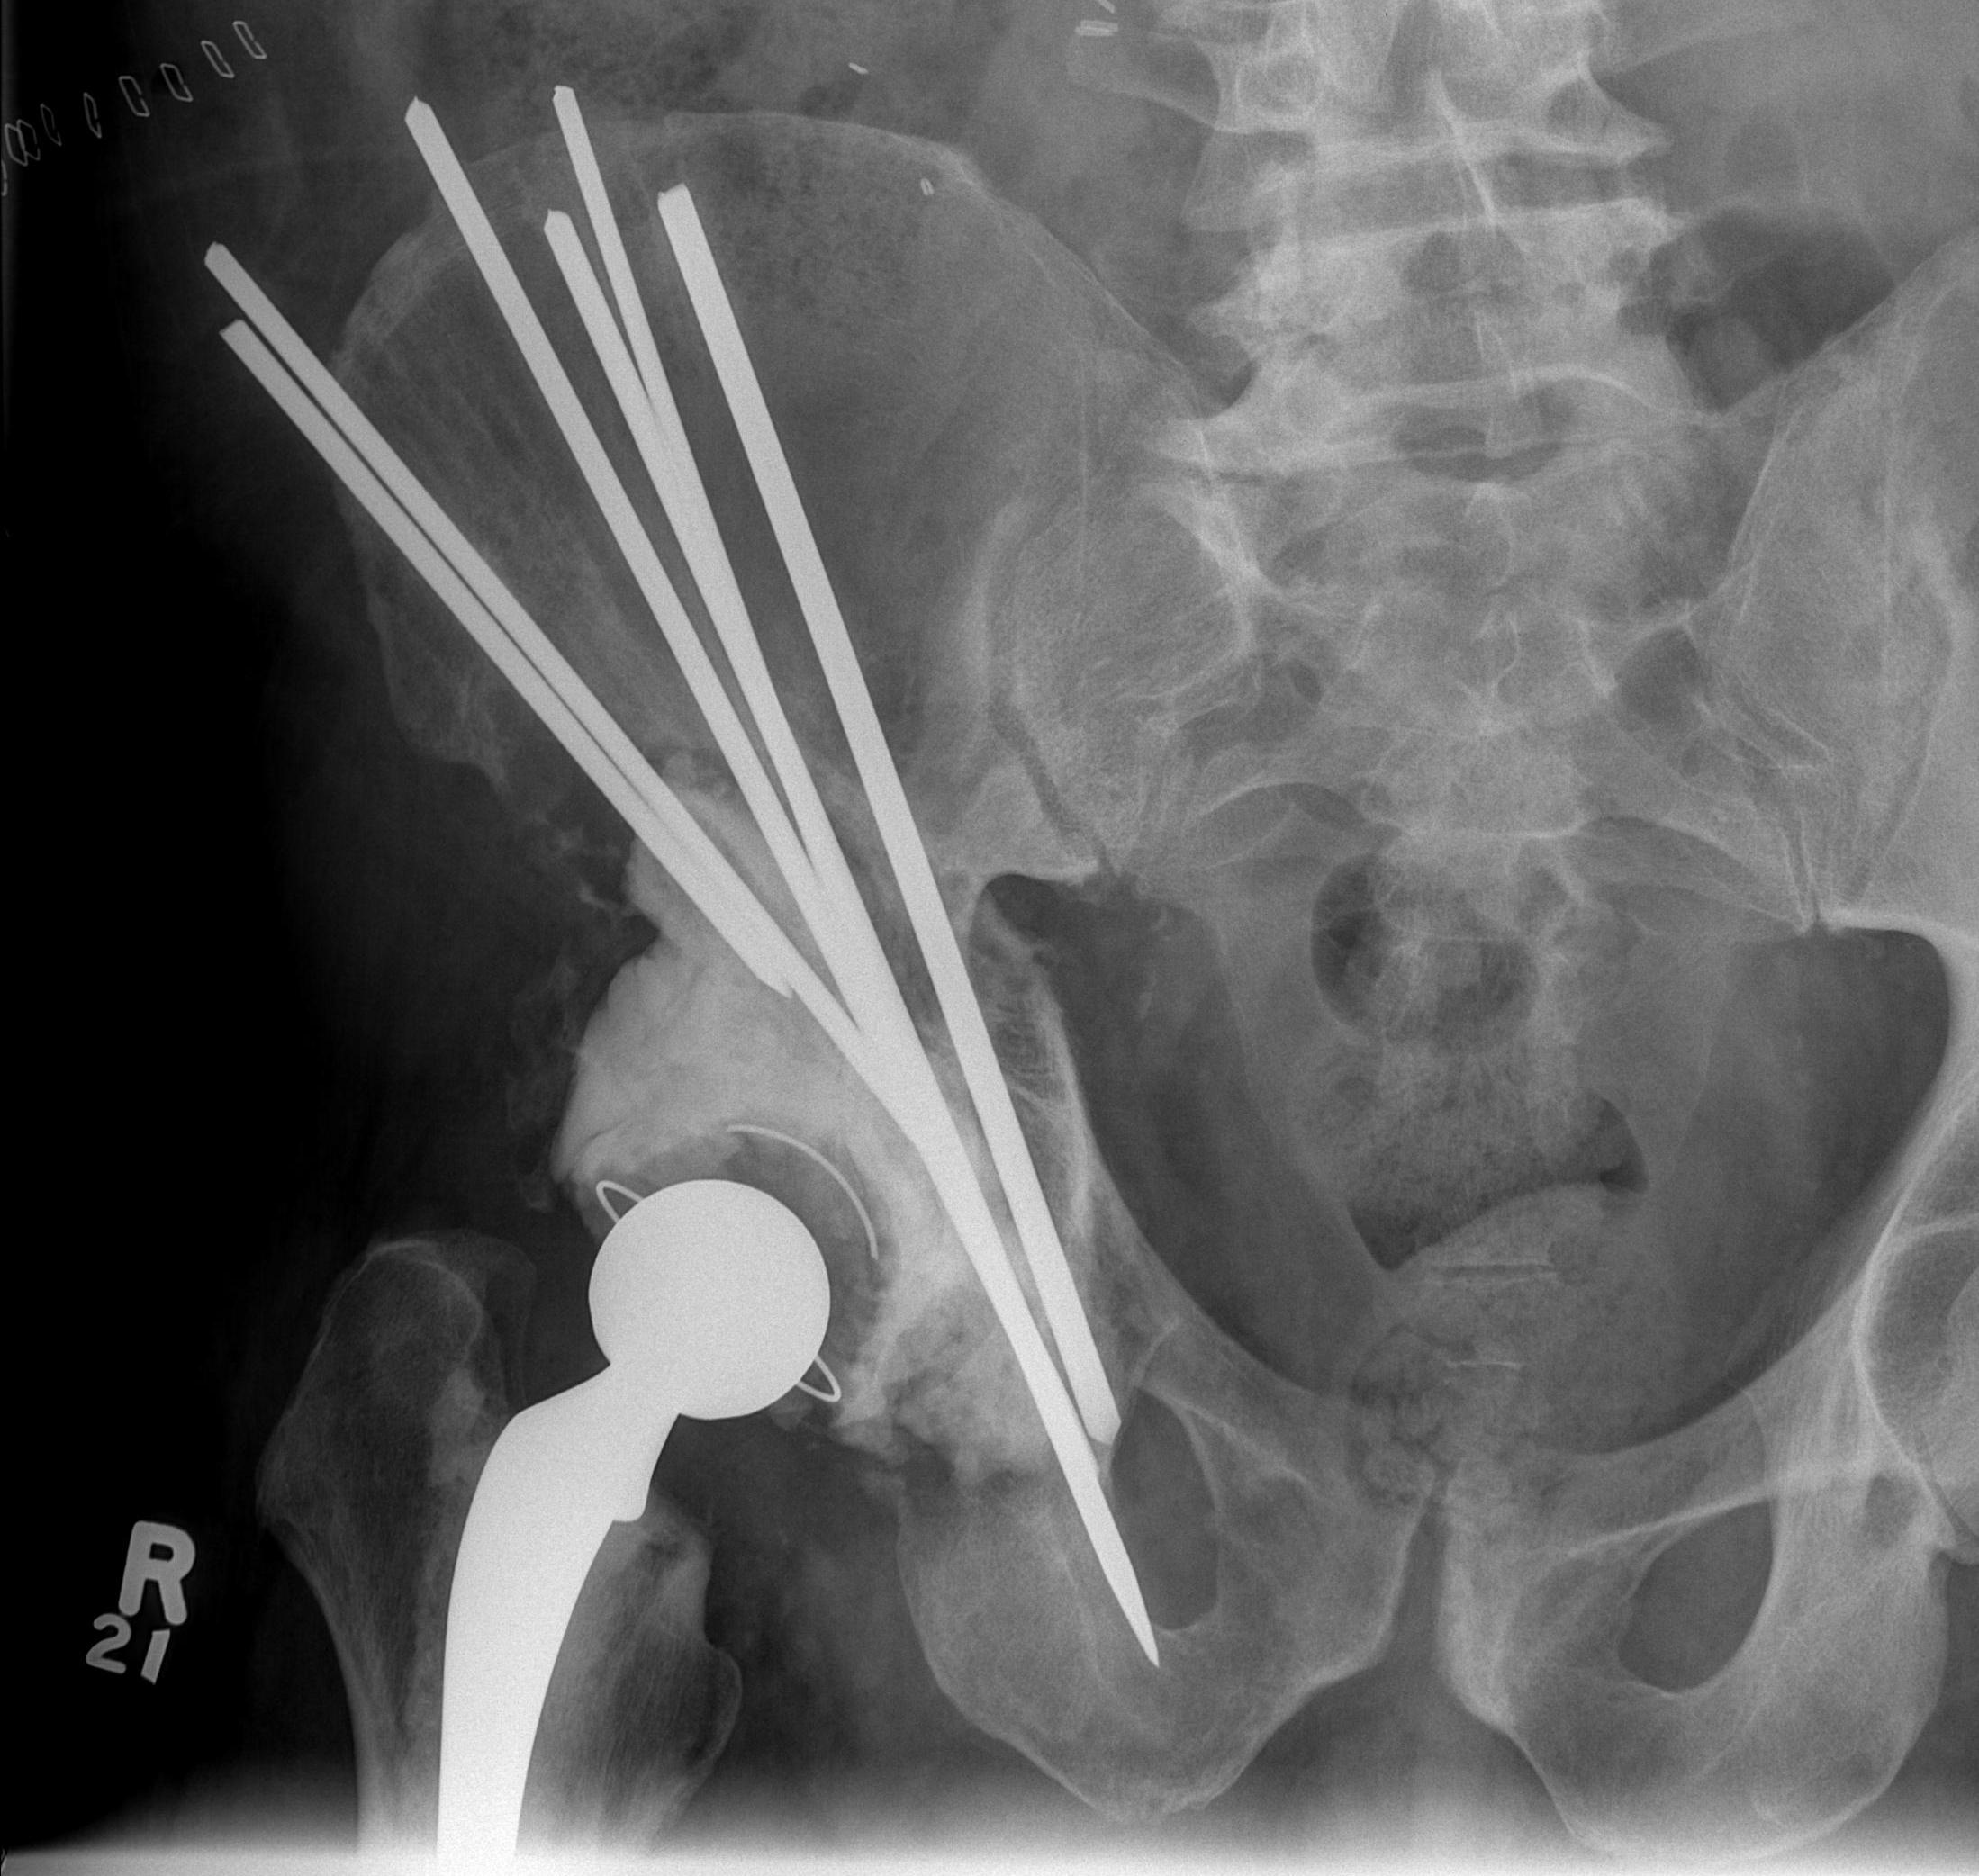

Cemented Harrington technique / steinmann pins

Harrington technique